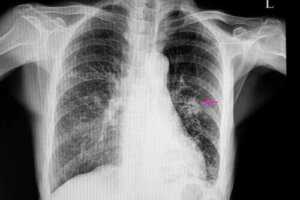

Bu gibi durumlarda, nodüller kötü tanımlanmış kenarları nedeniyle düzensiz bir görünüme sahip olacaklardır. Bu durum, röntgende görülebilir. Ayrıca, genellikle iyi huylu olanlardan daha küçüktürler. Bunun yanında, aşağıdakiler gibi belirli risk faktörlerinin bir parçasıdırlar:

Bunlardan sonra, bir doktorun nodülün yerini belirlemek için belli görüntüleme testlerini gerçekleştirmesi gerekir. Bunun yanı sıra, görüntüler, onların şekil ve boyut gibi belli özellikleri gözlemlemelerini sağlayacaktır. Bunun nedeni iyi huylu bir nodülü, olası kötü huylu bir nodülden ayırt etmede bu faktörlerin önemli olmasıdır.

Bunları teşhis etmenin en yaygın yolları göğüs röntgenleri ve bilgisayarlı tomografilerdir. Akciğer nodülünün kesin nedenini bulmak için hekimler bazen biyopsiler de yaparlar çünkü biyopsiler doktorların dokuyu analiz etmelerini sağlar.